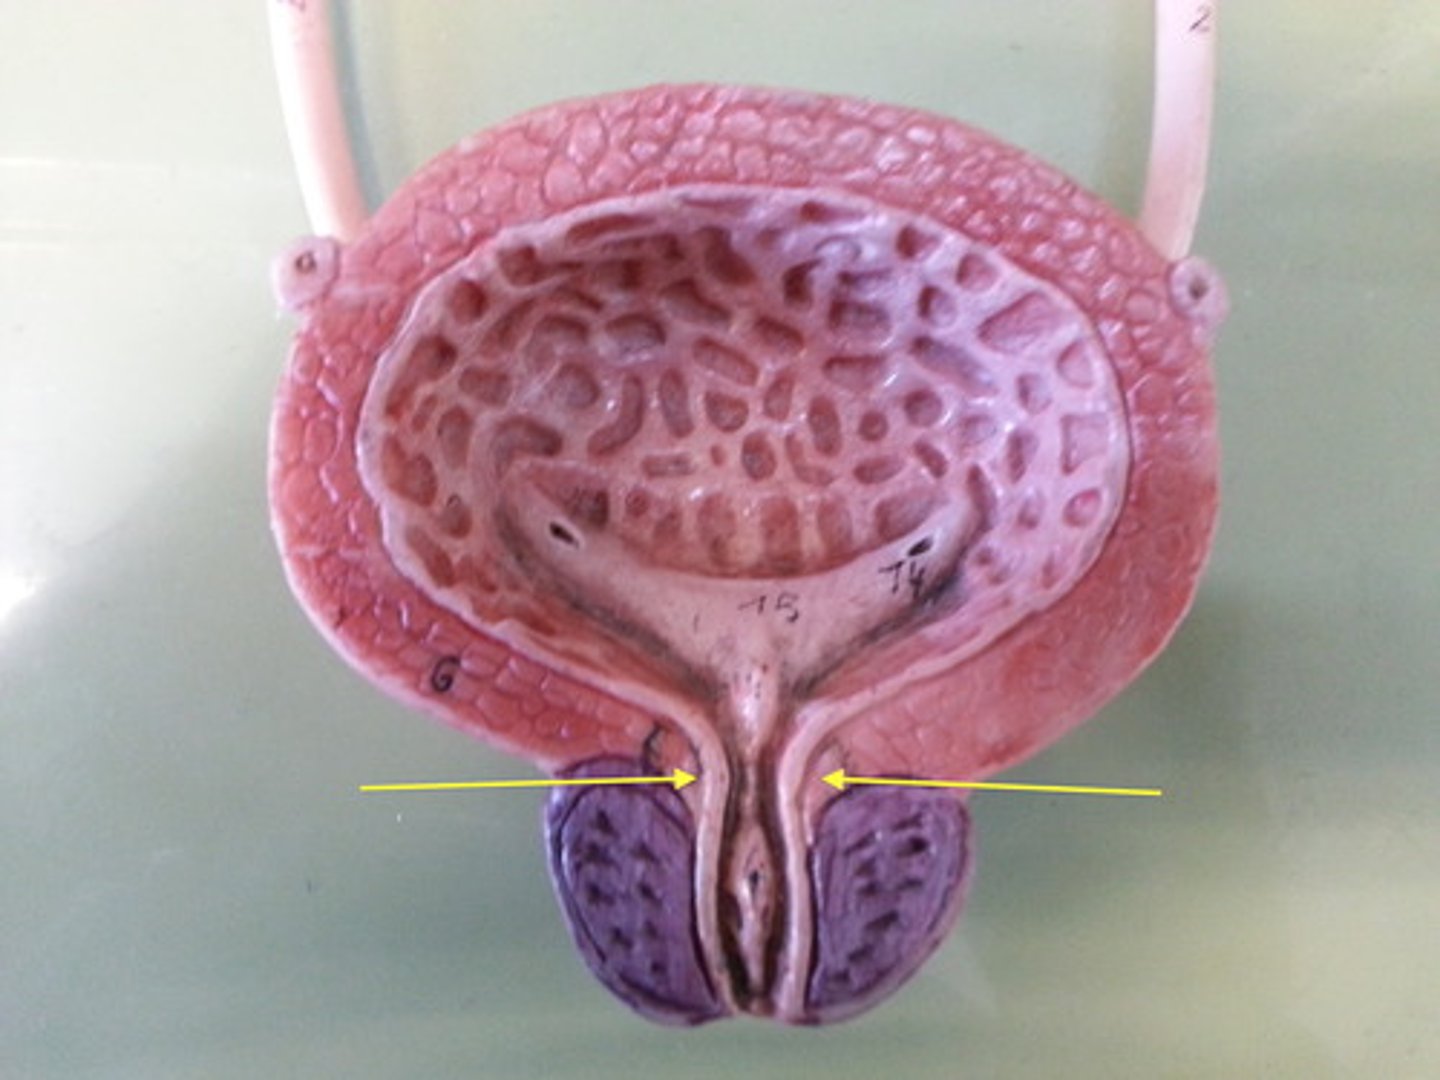

urinary bladder

urinary bladder

detrusor muscle

layer

internal urethral sphincter

bladder neck

external urethral sphincter

ureteric orifice

trigone of bladder

rugae

Urethra